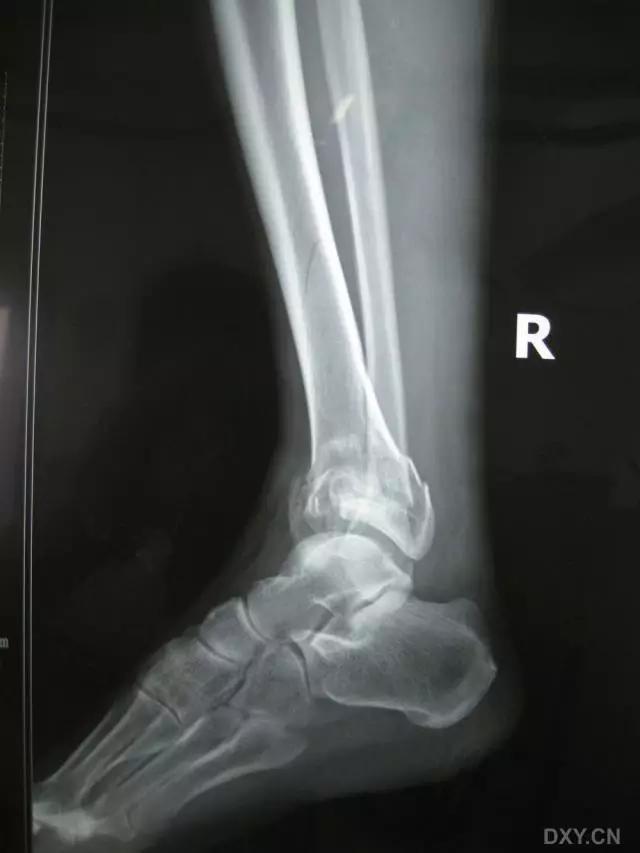

5. Maisonneuve 骨折

腓骨近端骨折伴内踝骨折及三角韧带断裂。

(来源:Radiopaedia)